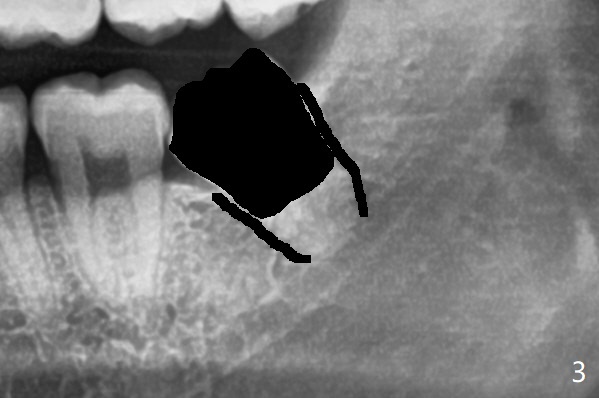

牙冠去除后(图三:黑色)